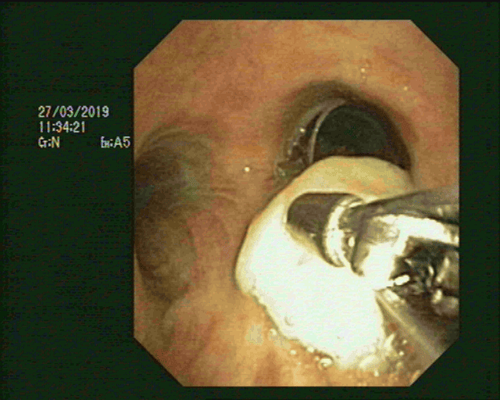

• Khi đưa ống soi đến Carina quan sát thấy vị trí dị vật tại phế quản trung gian bên phải.

Vị trí dị vật tại phế quản trung gian bên phải.

• Tiến hành quan sát đánh giá các phân thùy phế quản xung quanh và tiến hành đã lấy dị vật ra khỏi cây phế quản.

Lấy dị vật ra khỏi cây phế quản.

• Dị vật phế quản là một mảnh xương có chiều dài 1.5cm, cứng, có 1 đầu sắc nhọn. Theo đánh giá của các bác sĩ, khi bệnh nhân ho dị vật có thể di chuyển và làm xước, bội nhiễm và loét niêm mạc phế quản. Đối với những dị vật này, để lâu có thể gây ra biến chứng thủng, viêm mủ, áp xe trong phế quản.

Dị vật phế quản là một mảnh xương có chiều dài 1.5cm, cứng, có 1 đầu sắc nhọn.